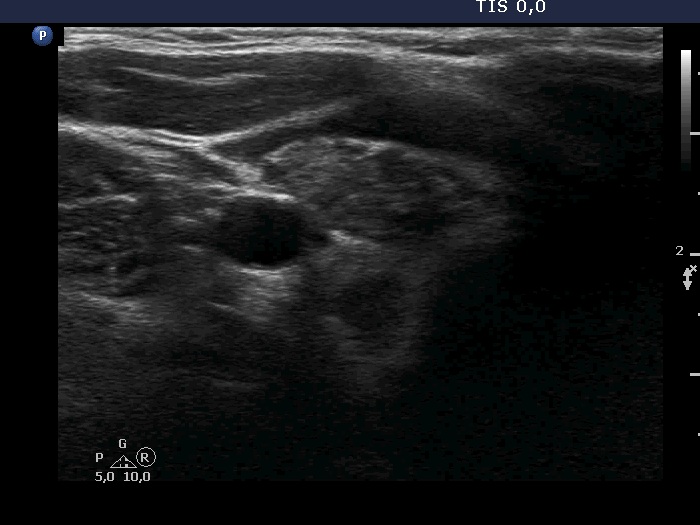

Ultrasonography. The thyroid was minimally hypoechoic and had more hypoechoic areas. There was a more hypoechoic nodule in the lower pole of the right lobe. The lesion has irregular, lobulated margins and numerous microcalcifications. A few microcalcification were found outside the core of the tumor. The intranodular vascularization was irregularly increased.

The ultrasound presentation of the nodule is very suspicious for papillary cancer. Indeed, this pattern is almost diagnostic.